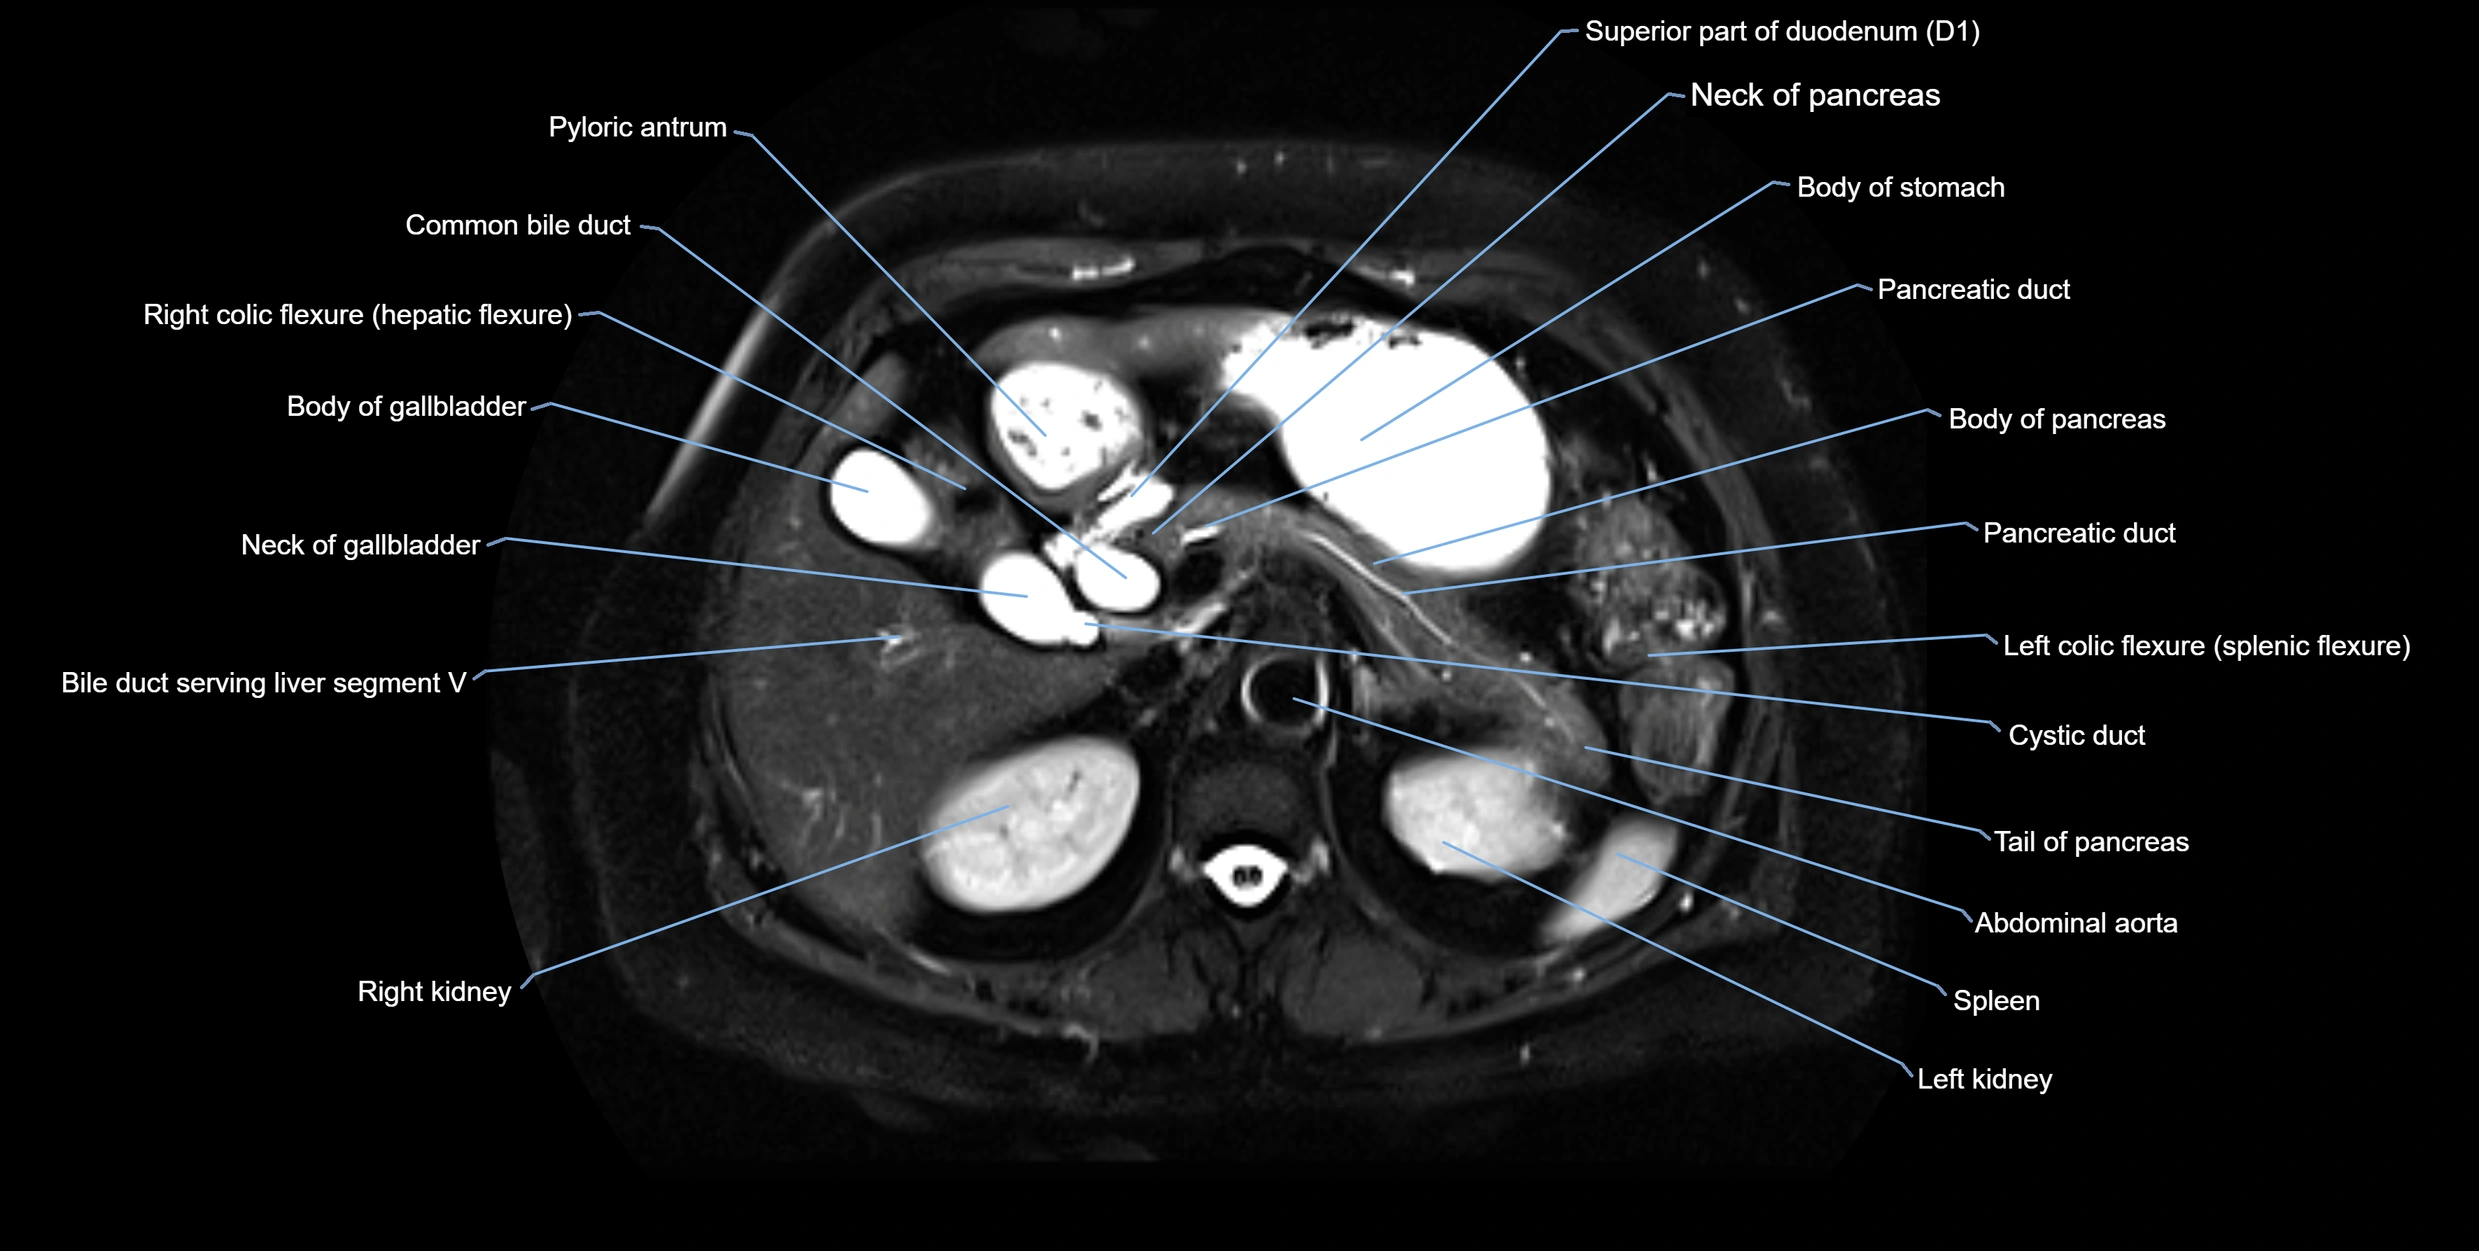

MRI Appearance

T1-weighted images:

• Not typically visualized unless dilated; appears as low signal tubular structure if seen

• Surrounding pancreatic parenchyma shows intermediate signal

T2-weighted images:

• Duct fluid appears bright

• Accessory duct seen as a fine high-signal tubular structure in pancreatic head

STIR (Short Tau Inversion Recovery):

• Duct fluid remains bright

• Surrounding fat suppressed, improving duct conspicuity

T1 Fat-Sat Post-Contrast:

• Normal duct does not enhance

• Surrounding inflammatory or neoplastic changes may enhance

T2 Fat-Saturated HASTE (single-shot):

• Accessory duct: bright, thin linear structure in pancreatic head

• Stones, strictures, or air bubbles appear as dark filling defects

• Excellent for rapid evaluation of duct patency

T2 TSE Fat-Saturated 3D (MRCP sequence):

• Duct visualized as a continuous bright tubular structure joining or parallel to the main pancreatic duct

• Allows 3D reconstruction of ductal anatomy and variants

• Excellent for diagnosis of pancreas divisum

Thick-slab T2 Fat-Saturated HASTE:

• Shows the accessory duct as part of the biliary–pancreatic system in a projectional image

• Highlights communication with main pancreatic duct and opening into the minor papilla

• Filling defects (stones, strictures) seen as dark spots within bright fluid

MRI image

image

Fullscreen Image